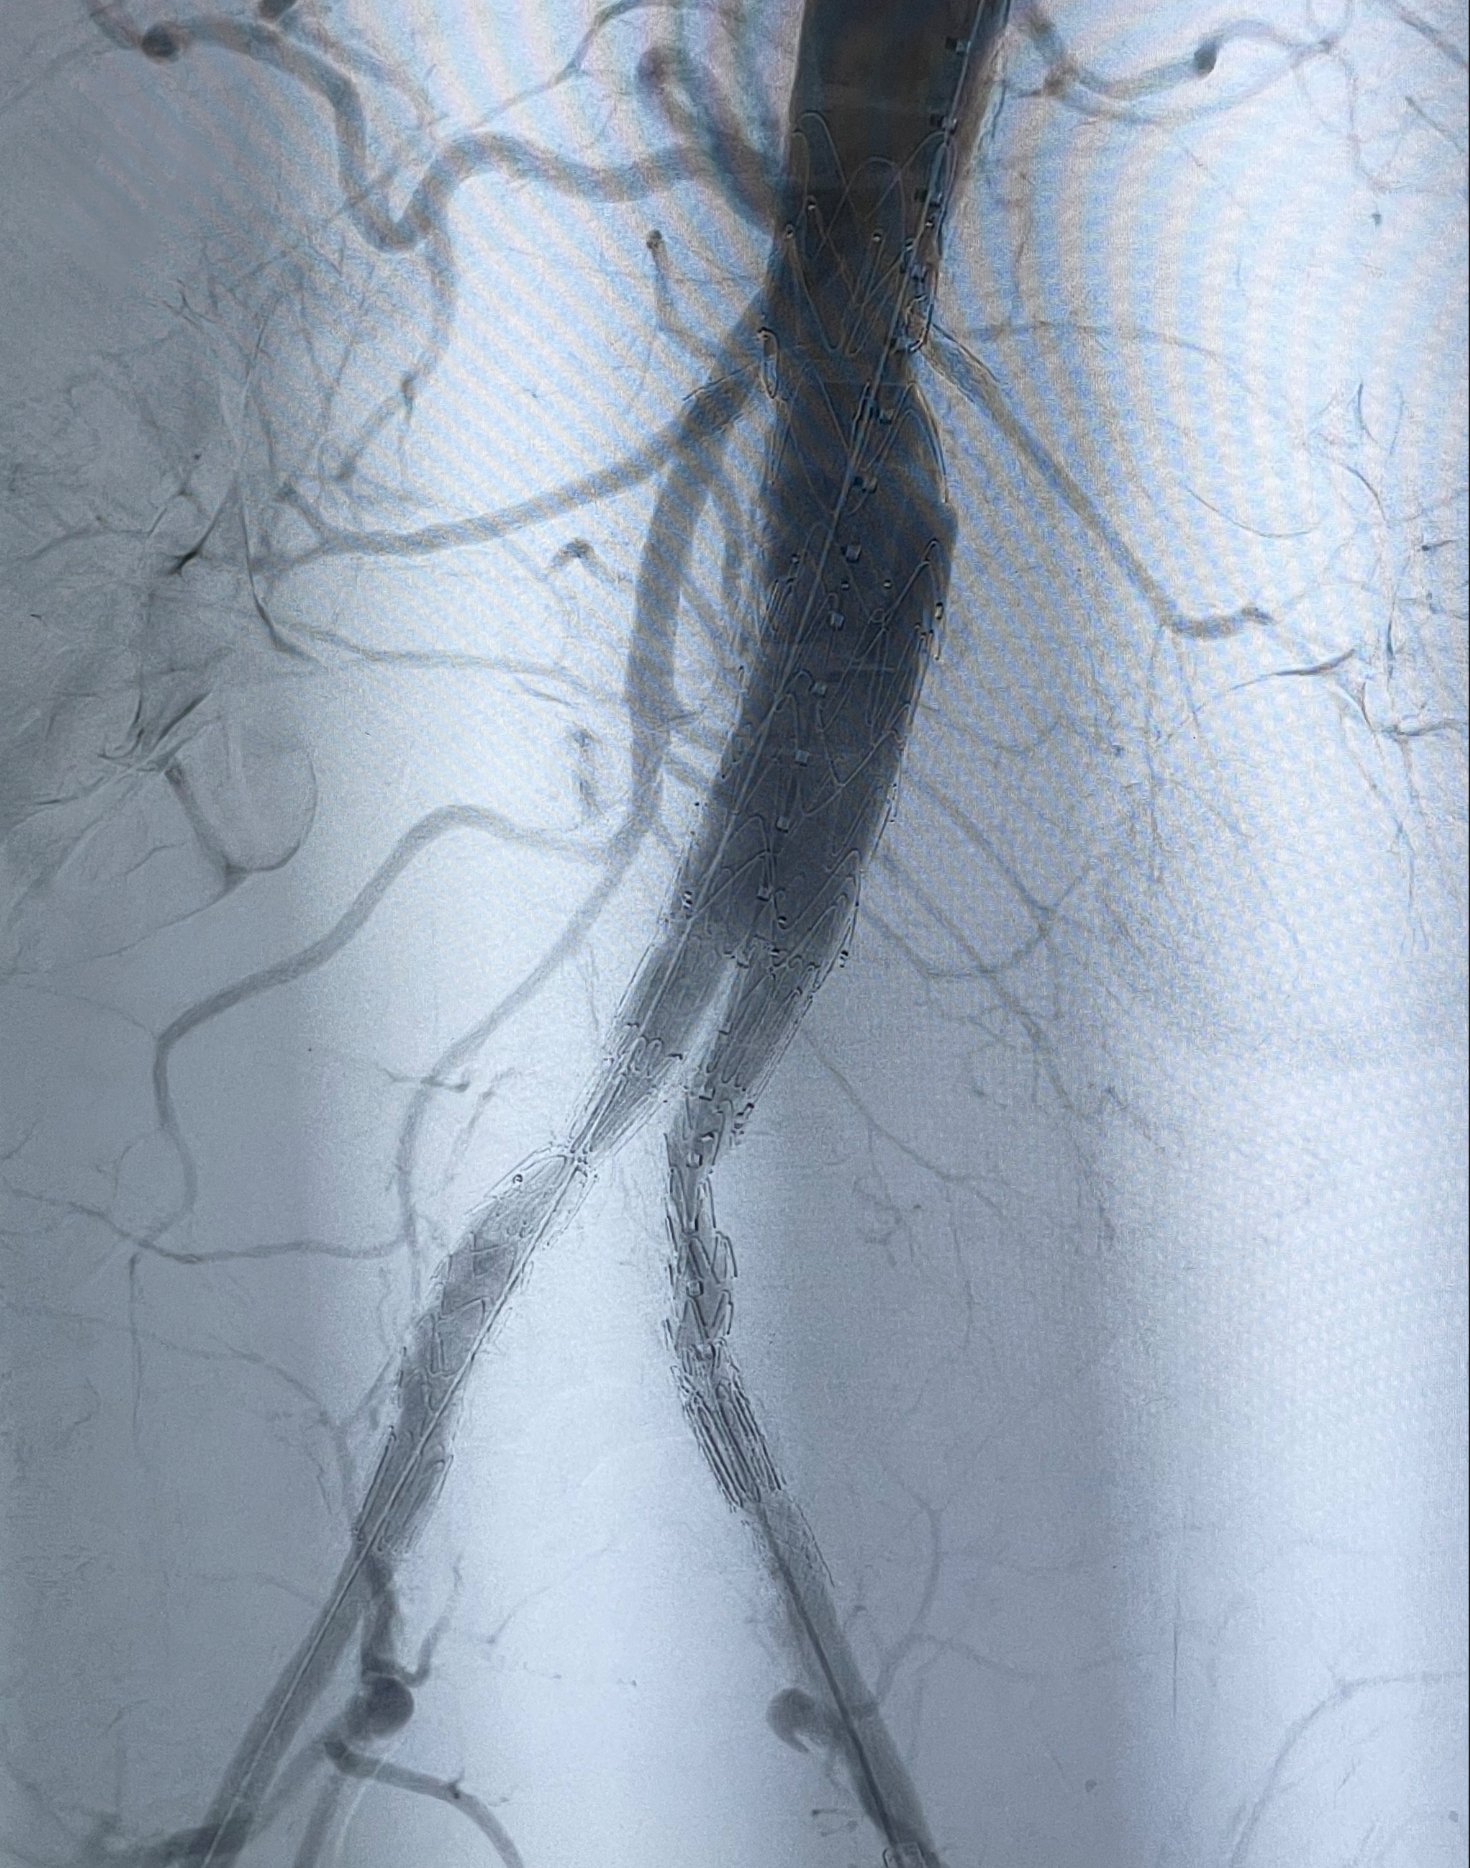

Endovascular Aneurysm Repair (EVAR) is a minimally invasive procedure that can be used to manage abdominal aortic aneurysms. EVAR uses small punctures and complex instruments to repair the bulges in the blood vessels (aneurysms). Left untreated, this can be a life-threatening condition. It is minimally invasive, requires a shorter hospital stay, and has a lower risk of complications.